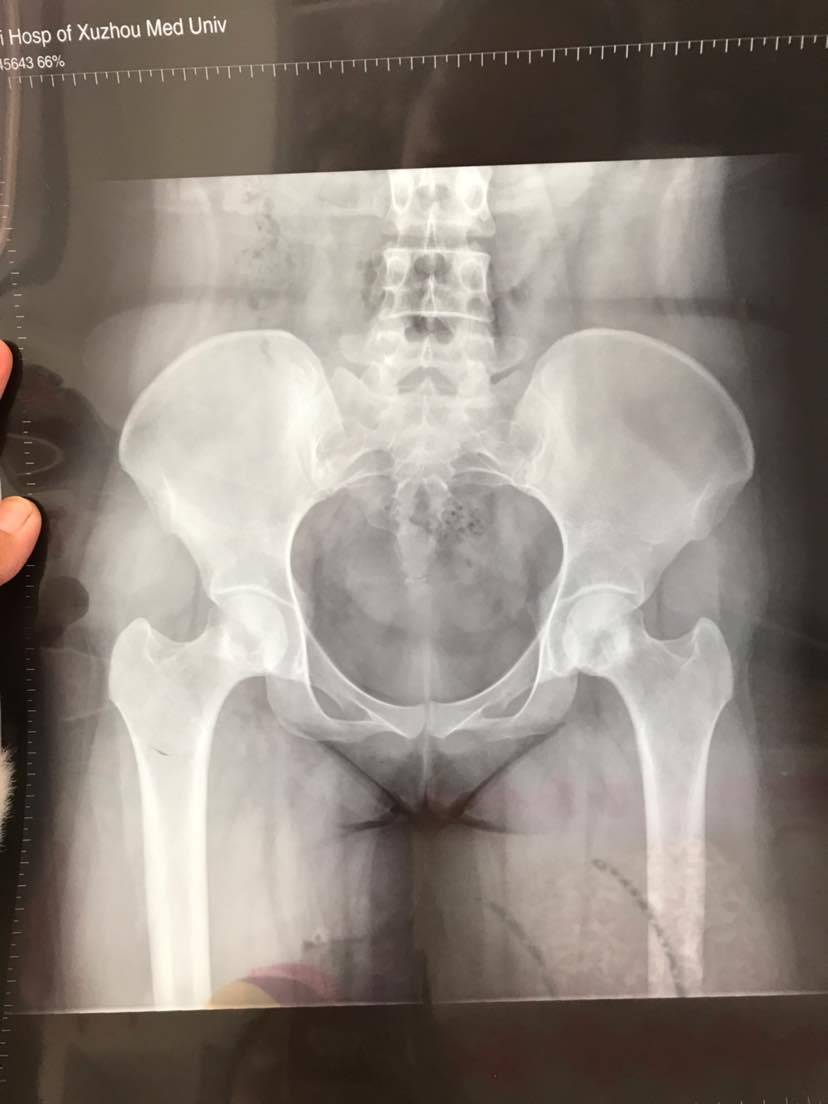

朋友们帮我看看这个报告!

是不是已经骨坏了

你第一张是X光片吗

是的,不过是前期比较轻的

骨坏不严重,还好,我都已经双髋关节置换了。

似乎是股坏了

好像是股坏了